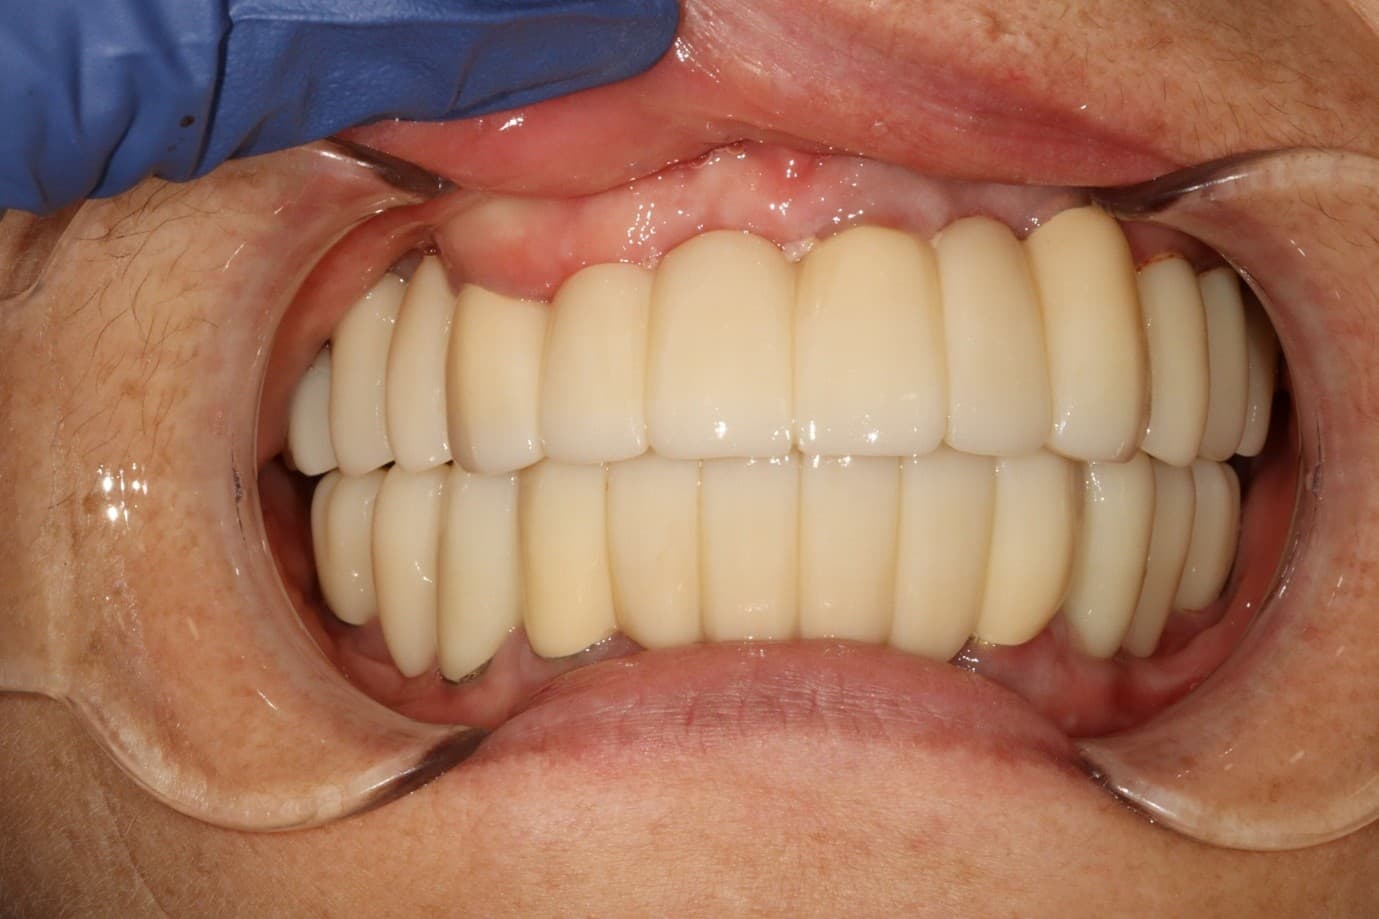

김○님님 치료 사례

치료 후

X-ray